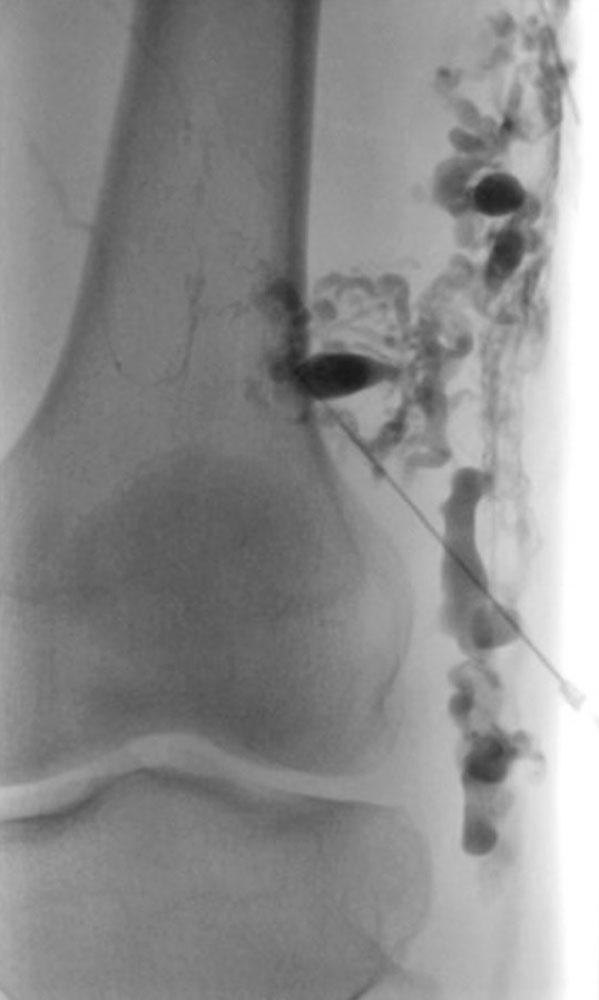

In some patients with previously untreated or insufficiently treated venous malformations, where there is a connection to the deep venous system (“communicating vein” or marginal vein) with a correspondingly increased risk of thrombosis or thromboembolism, the risk of this complication may be higher during pregnancy. Appropriate therapy before pregnancy with interventional or surgical closure of these communicating veins can significantly reduce or eliminate this risk. For some patients, longer-term anticoagulation with heparin may additionally be useful and necessary in consideration of the individual risk-benefit ratio during pregnancy. Data are available for patients with Klippel-Trénaunay syndrome, although the results were not entirely consistent. On the one hand, there was no difference in the frequency of complications between pregnant and non-pregnant women with Klippel-Trénaunay syndrome. Nevertheless, the risk of complications was increased compared to normal pregnant women, and the rate of postpartum bleeding was twice as high. In another study comparing Klippel-Trénaunay syndrome patients with non-pregnant women, 43% of KTS patients reported more symptoms during pregnancy. 6% experienced thrombosis during pregnancy and 2.3% experienced pulmonary embolism. Thus, the complication rate was significantly higher than for normal pregnant women.